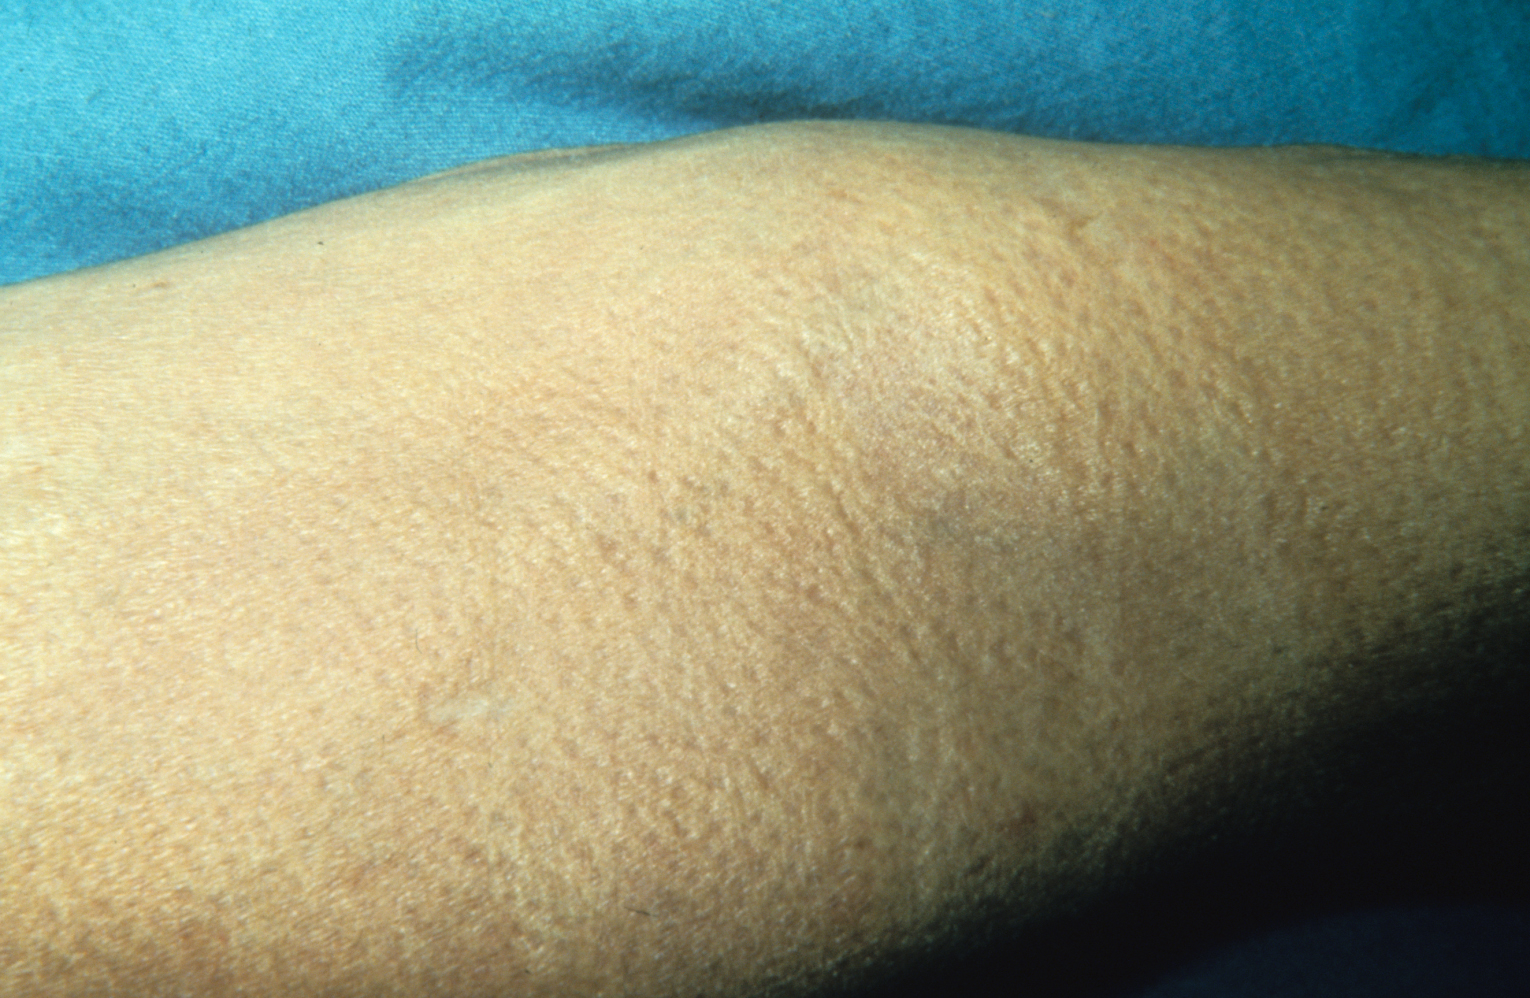

Медицинские исследования: эластическая псевдоксантома